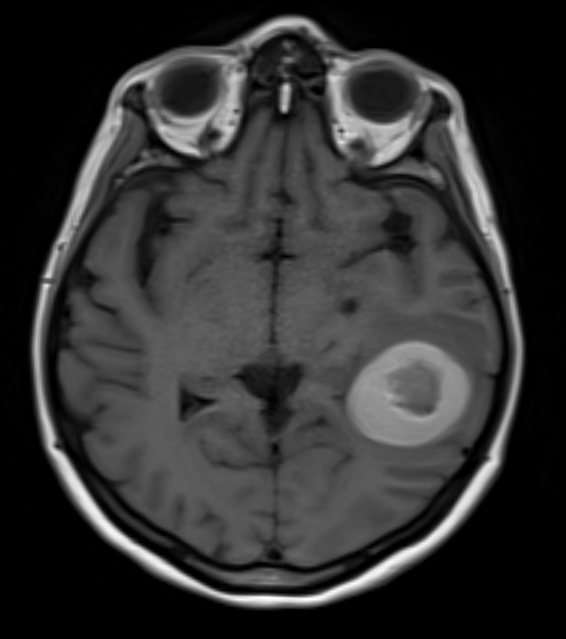

cavernome temporal

Figure 1. Cavernome temporal ayant saigné, en pré-opératoire